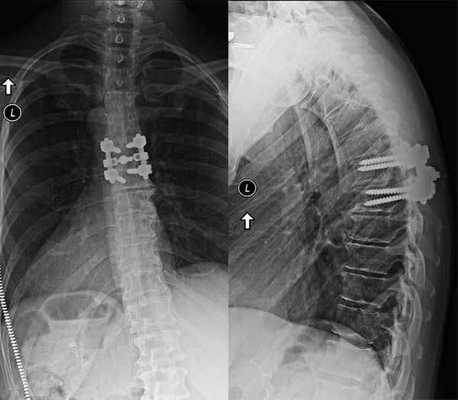

Сращение позвонков на рентгене.

Одним из способов стабилизации прооперированного позвоночно-двигательного сегмента является спондилодез. Его выполнение подразумевает установку специальных опорно-стабилизирующих конструкций, прочно соединяющих соседние позвонки в области воздействия между собой. В определенных случаях дополнительно требуется провести трансплантацию взятого у пациента из подвздошной кости фрагмента. В результате позвонки плотно срастаются между собой и теряют способность двигаться. Но при проведении ламинэктомии на 1 или 2 позвонках и их спондилодезе пациенты обычно не замечают существенных ограничений при движениях.